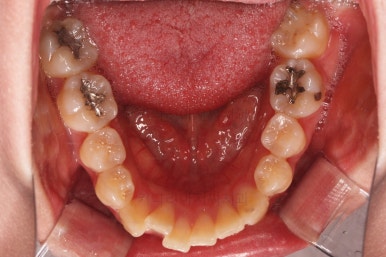

1. 초진

초진 시 입안의 모습입니다.

전반적으로 치열이 삐뚤고요.

위아래 중앙선이 약간 틀어져 있는데 많이 심한 편은 아니고요. 윗니가 배열된 U자 형태를 보면 아랫니보다 좁은 형태로 "악궁이 좁은" 상황이었습니다.